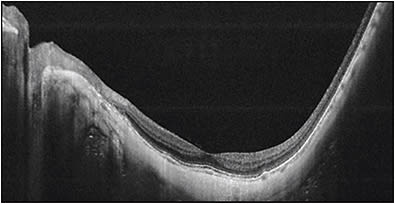

The most common methods to detect staphylomas have been color fundus photography and ultrasonography. Especially, conventional 50° fundus photos are widely used in many epidemiological studies. However, most staphylomas involve wide areas of the fundus (especially the upper and temporal direction), and thus the entire extent of the staphyloma does not fit within the 50° field of view of conventional fundus photographs (Figure 2). Similarly, in most cases, staphylomas are too wide to fit into the length of an OCT scan (Figure 3).

To solve these issues, we are conducting ongoing studies using a prototype ultra-widefield OCT by Canon Inc. (Tokyo) in our institute. In the near future, this technique will become a cost-effective and more available tool to evaluate the presence and types of staphyloma. Different from 3D MRI, widefield OCT can also visualize how the retina and optic nerve are damaged by eye deformity (Figure 5). This is important because it can demonstrate the exact cause of vision-threatening complications in pathologic myopia.